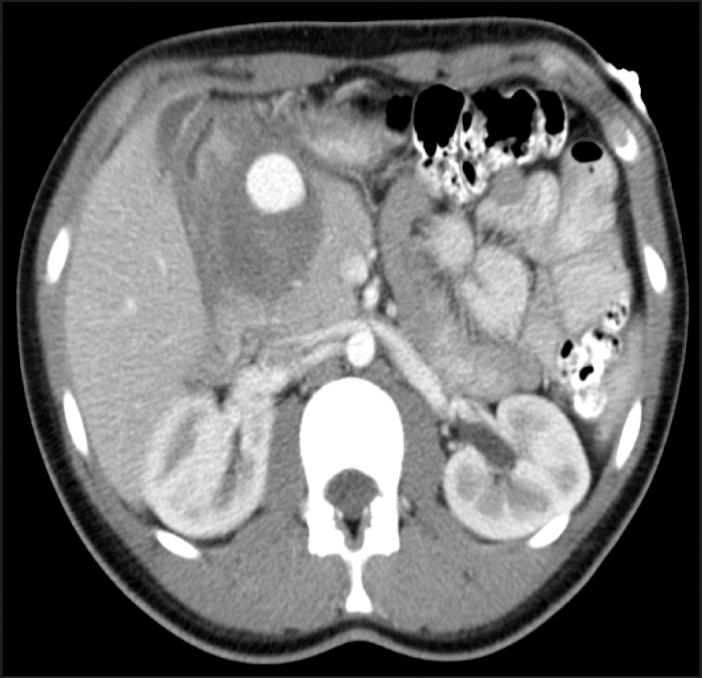

Hemosuccus pancreaticus (HP) is a rare cause of gastrointestinal bleeding (GIB) that should be considered in a patient with a history of pancreatitis and GIB. A 17-year-old female presented with nausea followed by an episode of hematemesis. Fourteen weeks prior to presentation, she had 3 episodes of vomiting within a week. Six weeks prior to presentation, she developed abdominal pain and was diagnosed with acute idiopathic pancreatitis. Computed tomography (CT) revealed a cystic lesion arising in the gastroduodenal artery (GDA), and coil embolization was performed. There are no reported cases of HP in an adolescent with acute idiopathic pancreatitis.